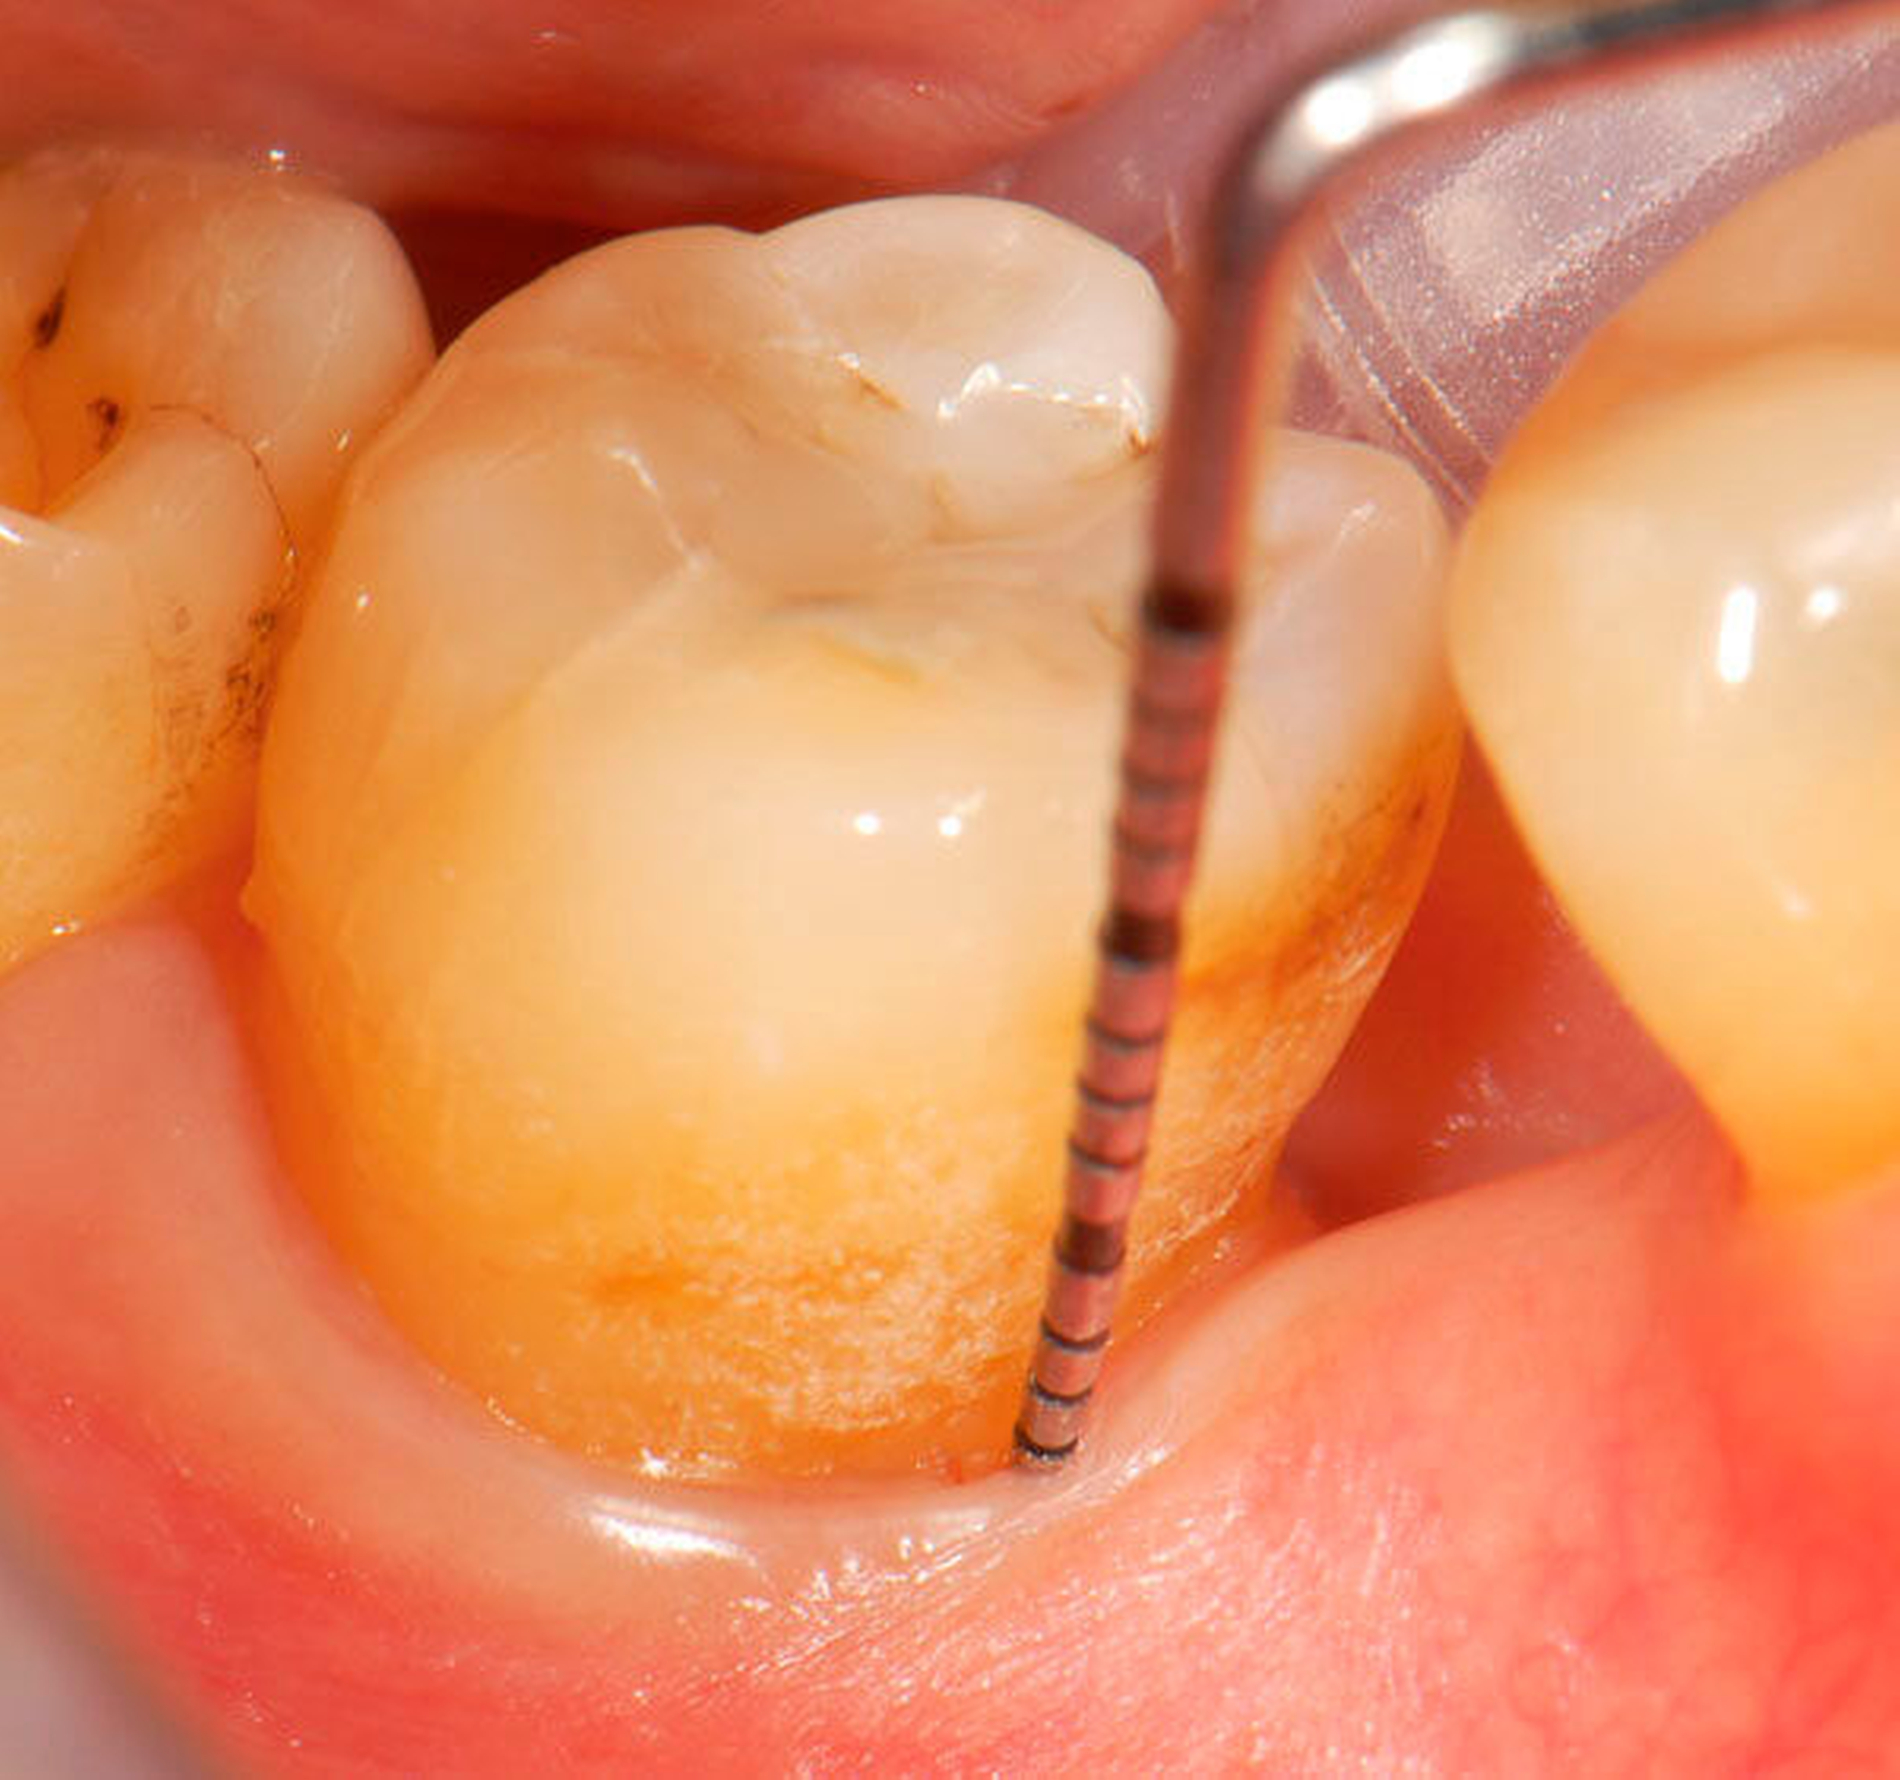

Abbildung 2: Direkte Teilüberkronung im Seitenzahnbereich (R1-Technik)

In den Abbildungen 1 bis 3 werden Optionen für frugale Interventionen auf restaurativem Sektor aufgeführt. Es handelt sich um direkte Vollüberkronungen im Frontzahnbereich (hier: hergestellt in R1-Technik / einphasig) (Abbildung 1), direkte Teilüberkronungen im Seitenzahnbereich (hier: hergestellt in R1-Technik / einphasig) (Abbildung 2), Reparatur-Restaurationen im Seitenzahnbereich (hier: hergestellt in R2-Technik / zweiphasig) (Abbildung 3). Technische Einzelheiten zur Vorgehensweise und den Ergebnissen sind an anderer Stelle beschrieben (Literatur siehe oben).

Für die in Abbildung 2 dargestellte Situation eines tief zerstörten Prämolaren gelten ähnliche Charakteristika. Es gibt in der restaurativen Zahnheilkunde viele Neuerungen, die das Behandlungsspektrum vergrößert haben. Dazu zählen unter anderem: